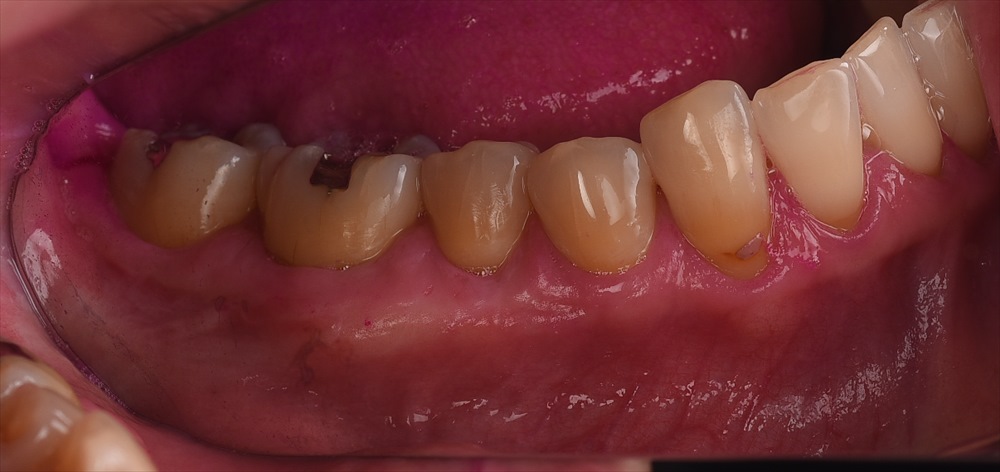

術後1ヶ月

全くしみなくなって快適!!

と喜んで頂けました。